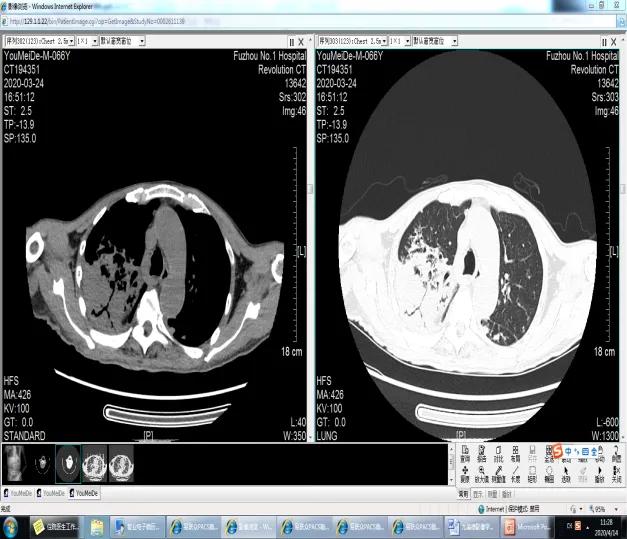

尤大爷66岁了,身体一直很好,但从去年农历12月开始,出现咳嗽、咳痰,伴咯少量鲜红色痰,疲乏无力、吃不下饭。开始老人家没太重视,在诊所看了几次,没效果。大年三十开始出现发热,体温达到39度,由于新冠肺炎疫情一直不敢去医院,正月初三老人家实在受不了才到当地医院治疗。刚开始医生还担心是新冠肺炎,经CT检查怀疑是肺癌,肺脓肿可能。给予抗感染、化痰止咳等治疗,患者仍持续发热,还出现了气喘,状态每况日下。在当地医院治疗效果不佳,也没办法进一步明确病因,经街坊邻居(曾在我科诊断肺隐球菌病)推荐来我院就诊。当时新冠肺炎疫情严重,家属联系到了我院呼吸科徐礼裕主任,在院排除新冠肺炎后,正月初十,患者转入我科。转入后,经认真询问病史,详细阅读患者的胸部CT及其他检查结果,我们考虑肯定存严重感染,且肺癌的可能性也很大。

肺肉芽肿性多血管炎(granulomatosis with polyangiitis, GPA)是一种免疫介导的复杂疾病,起始的炎症反应和高度特异性免疫应答相互作用,从而导致组织损伤与ANCA相关。GPA肺部影像学表现称为“三多一洞”,主要是以两侧肺内多发性、多形性和多变性的结节或肿块影,可有空洞.也可见磨玻璃影、肺不张或支气管束增宽支气管狭窄等。常需要与肺结核、肺曲霉菌感染、肺部肿瘤、显微镜下多血管炎、嗜酸性肉芽肿性多血管炎等疾病鉴别。GPA的初始免疫抑制治疗通常是糖皮质激素联合环磷酰胺或联合利妥昔单抗。维持治疗:一旦环磷酰胺或利妥昔单抗治疗诱导缓解后(通常在3-6个月内),即可换为通常毒性较弱的其他免疫抑制药物行维持治疗,常用的药物包括硫唑嘌呤、利妥昔单抗、MMF或甲氨蝶呤。未得到治疗的全身性GPA患者2年时死亡率高达90%,死因通常为呼吸或肾脏衰竭。